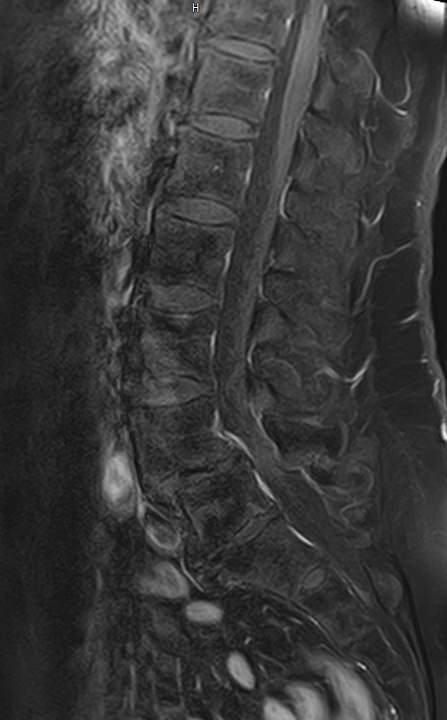

Магнитно-резонансная томография является современным, высокоинформативным и доступным методом обследования позвоночника. МРТ позволяет оценить состояние костных структур позвонков, спинного мозга, нервных корешков и окружающих мягких тканей. С помощью МРТ можно диагностировать грыжевые выпячивания межпозвонковых дисков, степень их воздействия на нервные корешки и спинной мозг.

Но несмотря на высокую диагностическую ценность магнитно-резонансной томографии, в некоторых случаях для улучшения визуализации патологических очагов дополнительно применяется контрастное усиление. В частности, при подозрении на опухоли позвоночника или спинномозгового канала, для оценки активности очагов демиелинизации спинного мозга, требуется внутривенное введение контраста.

В клинике «Доступная медицина» выполняется МРТ различных отделов позвоночника. В зависимости от уровня поражения можно провести МР томографию шейного отдела, грудного отдела, пояснично-крестцового отдела позвоночника и копчика.